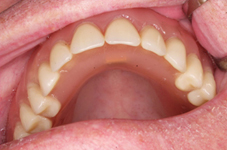

Náhrada jednoho zubu

Klasickým příkladem a indikací pro použití implantátu je ztráta jednoho zubu (v tomto případě v předním – frontálním úseku) v jinak zdravém, nepoškozeném chrupu.

Nejčastější příčinou takové ztráty je sportovní nebo dopravní úraz.

Náhrada jednoho zubu pomocí implantátu je možná také v postranním úseku chrupu. Při ztrátě většího počtu zubů ve frontálním nebo postranním úseku může být mezer uzavřena větším počtem jednotlivých implantátů.

Při ošetření pomocí jednotlivých implantátů zůstávají sousední zuby neporušené – intaktní. Při klasickém ošetření pomocí můstků musejí být tyto zuby obroušeny!